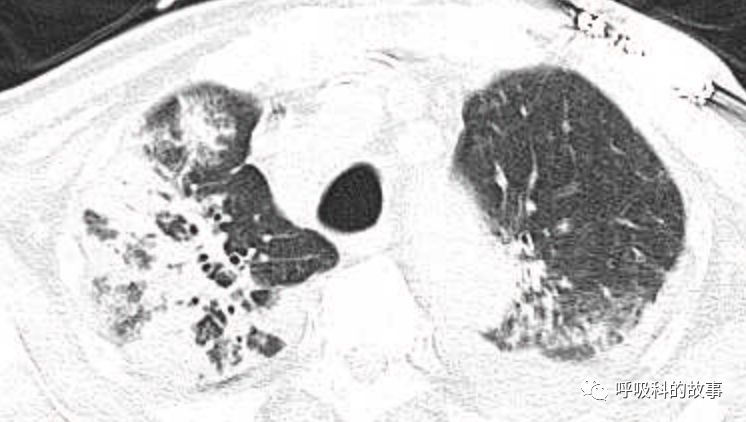

肺部CT如下:

以上的CT给我第一眼的感觉是肺炎,再结合患者有发热和血炎症指标明显增高,肺炎的诊断应该没有问题,但是胸水又是漏出液,结合脑钠肽增高和患者有胸闷气急的症状,心功能不全的诊断也能成立。在某些层面,肺部实变影以内中带为主,还要考虑肺水肿的诊断。入院后给予患者美罗培南抗感染、托拉塞米利尿治疗,以及化痰、雾化处理,患者体温在入院后三天就正常了,入院第五天复查NT-proBNP3390pg/ml;血常规示白细胞 13.5*10^9/L,中性粒细胞81.8%,淋巴细胞13.2%,超敏C-反应蛋白 25mg/L;电解质示钠 160mmol/L,氯 111mmol/L 。虽然炎症指标和心功能指标均有好转,但患者却仍旧精神差,每次查房时仍然表现嗜睡状,家属也反映患者不论白天还是夜晚多数时间不是太清醒。那么问题出在哪里呢?